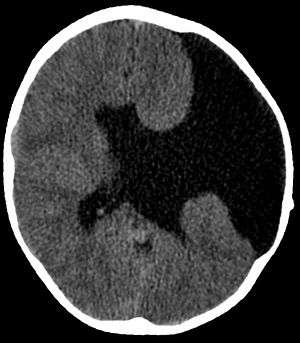

| Axial CT scan showing schizencephaly in a 6-year old child | |

Schizencephaly (from Greek skhizein, meaning "to split", and enkephalos, meaning "brain")[1][2] is a rare birth defect characterized by abnormal clefts lined with grey matter that form the ependyma of the cerebral ventricles to the pia mater. These clefts can occur bilaterally or unilaterally. Common clinical features of this malformation include epilepsy, motor deficits, and psychomotor retardation.[3]